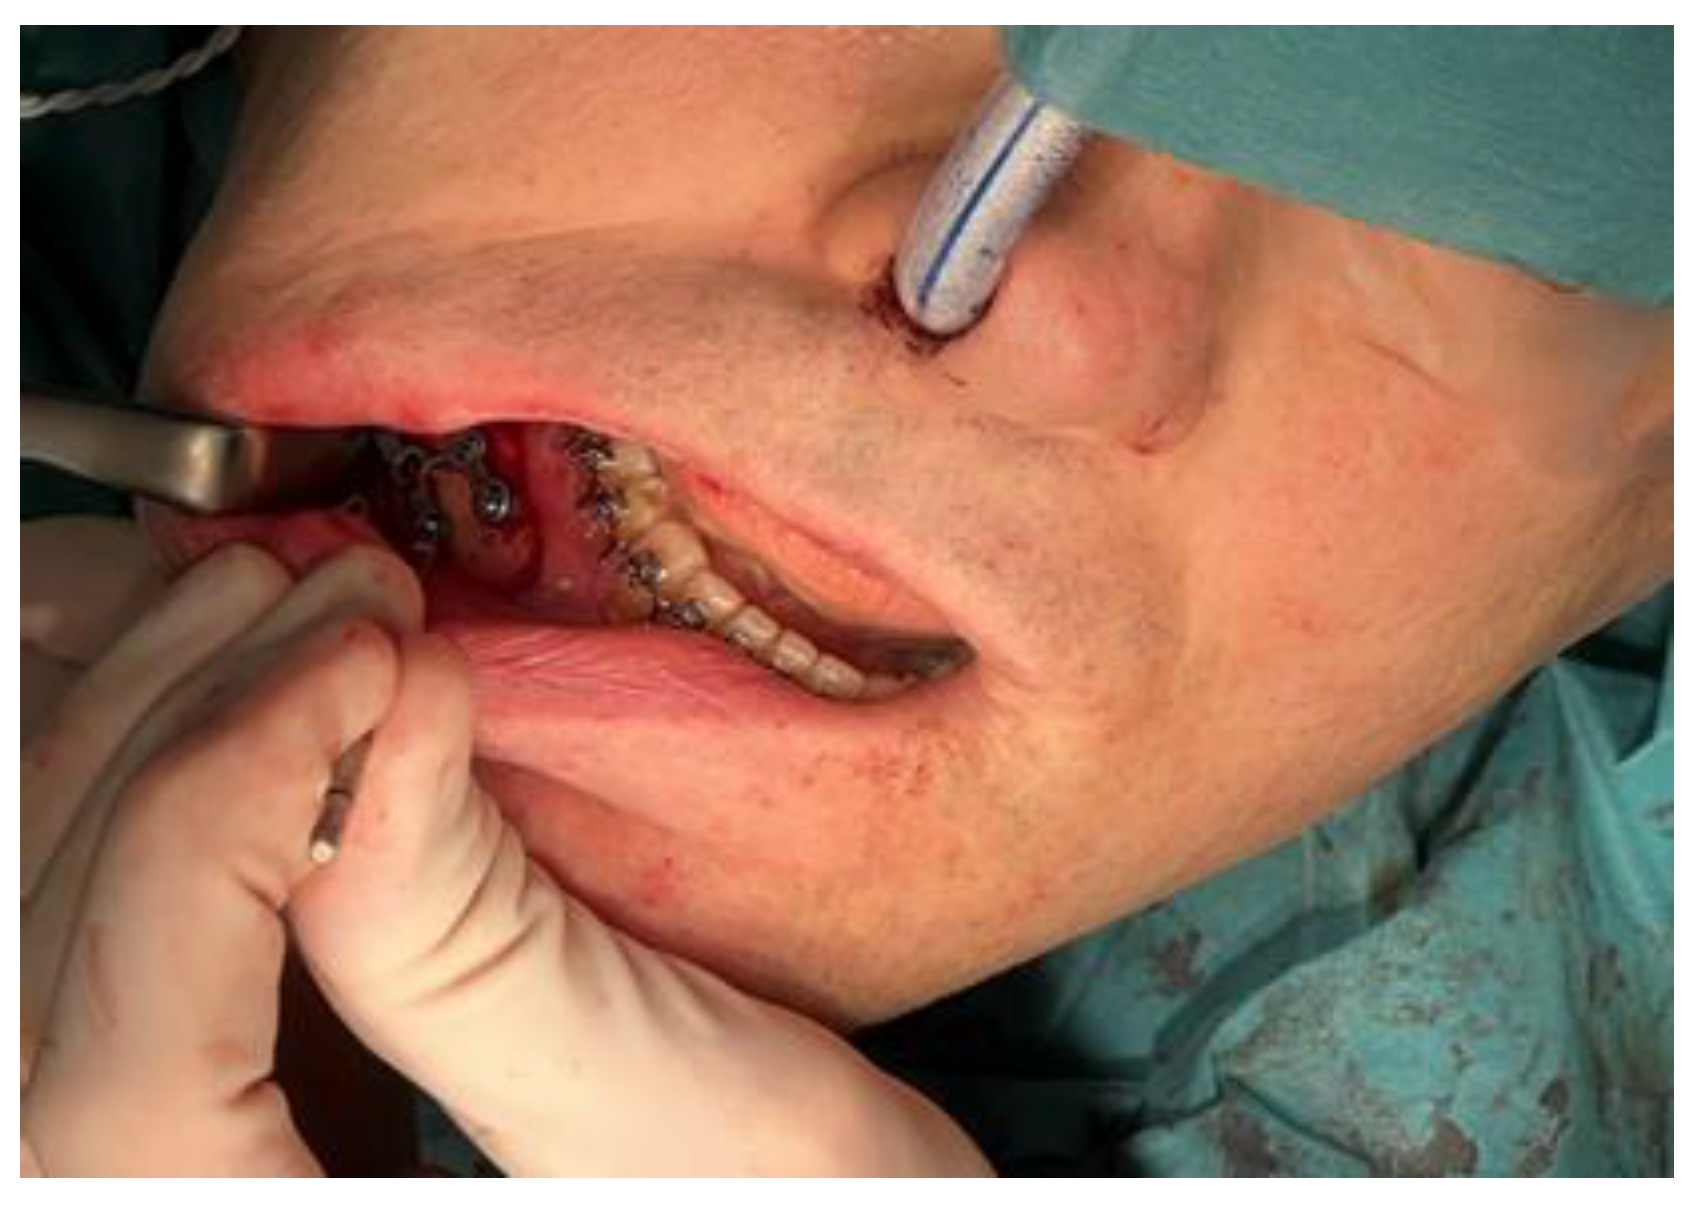

2.3.1. Mandible